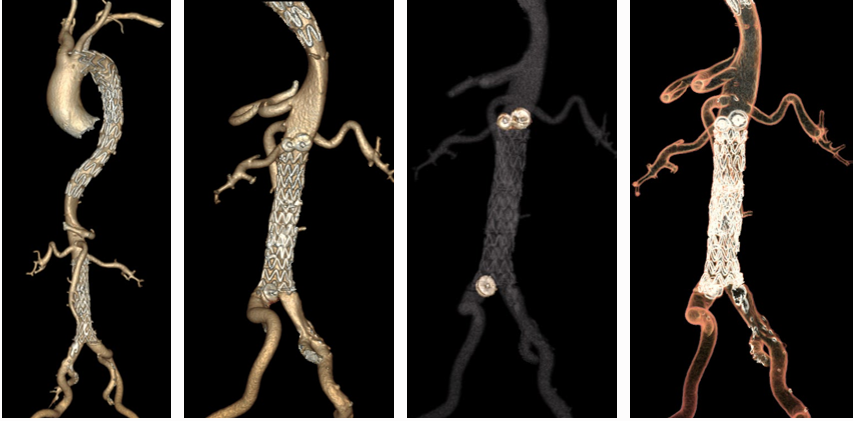

★ WeFlow-EndoPatch腔内补片系统

1.手术步骤:

2. 临床试验(N=27)

安全性:术后30天主要不良事件(MAE)发生率仅3.7%(1例因新冠肺炎呼吸衰竭)

有效性(术后6个月,n=15):

15例患者完成术后6个月CTA影像学随访。15例患者术前胸主动脉假腔最大直径 33.61±26.95 mm,术后6个月胸主动脉假腔最大直径缩小为 28.92±24.22 mm;术前腹主动脉假腔最大直径 25.96±7.27 mm,术后6个月腹主动脉假腔最大直径缩小为 22.07±5.69 mm。

*15例患者共植入29枚补片

15例患者术后6个月胸降主动脉段及腹主动脉段假腔均实现血栓化。

★ WeFlow-EndoSeal™假腔栓塞系统(N=11)

持续假腔血流被认为是TEVAR/EVAR术后动脉瘤样退变的原因。EndoSeal™系统是中国人民解放军总医院第一医学中心血管外科郭伟教授团队自主研发的,一种用于假腔栓塞的设备,能有效阻断假腔回流,促进主动脉重塑。

临床试验早期结果:

纳入11例患者,7例完成术后30天内CTA随访

术后30天假腔100%部分血栓化,真腔直径扩大(12.09→14.53mm),假腔最大直径稳定

1例严重不良事件(术后113天内漏栓塞)